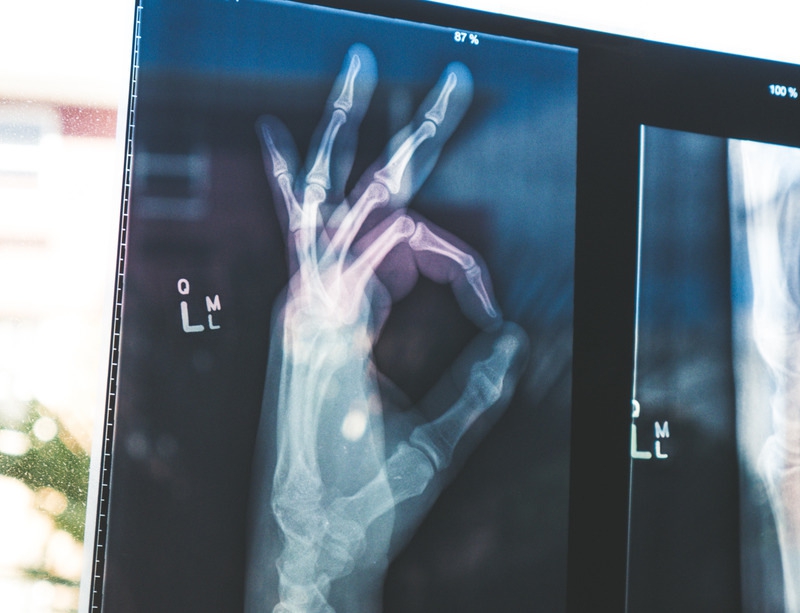

4. Rontgen Thorax

Rontgen thorax adalah teknik medical check up dengan pemeriksaan radiologi (khususnya sinar X-Ray) pada area dada. Hasil dari rontgen thorax dapat melihat gambaran serta evaluasi atas kondisi paru-paru, cairan di rongga dada, jantung, saluran pernapasan, tulang payudara, tulang rusuk, dan diafragma.